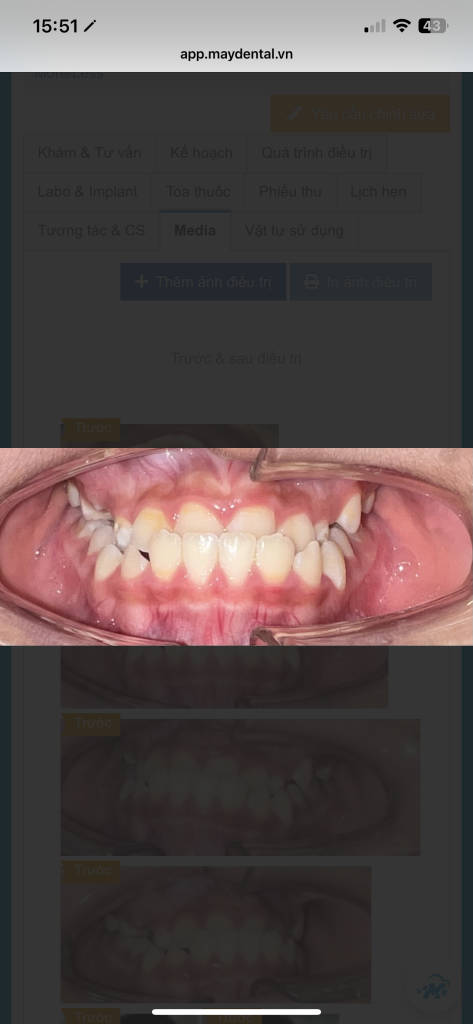

👶 Nhiều bé có tình trạng hàm trên kém phát triển, dẫn đến răng cửa dưới cắn ra ngoài (giống như bị móm). Nếu để lâu, khuôn mặt bé có thể mất cân đối và khó điều trị hơn sau này.

Hình ảnh trước và sau 2 tháng điều trị